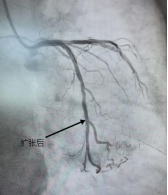

一位中年男性,因“胸闷气促”入院,此次发病后冠脉造影提示前降支中远段狭窄80%。心内科团队经过精准评估后发现,患者血管直径只有2.5mm,没有植入新支架,而是用药物球囊扩张成形术解决问题。手术成功打通狭窄血管,实现血运重建,患者体内未增加任何金属异物,有效缓解了患者病痛。